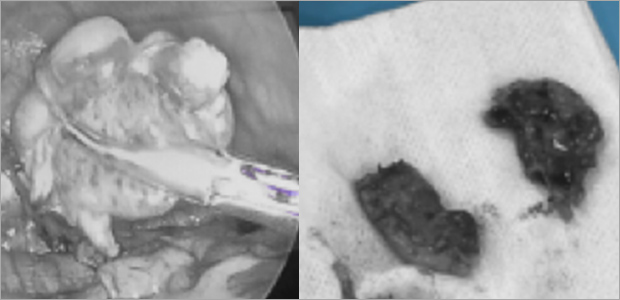

복강경 간생검

강아지 간생검 검사는 간질환의 원인을 알 수 있는 가장 정확한 검사입니다.

복강경 장비를 사용해 1cm이하의 절개창을 내어 간조직을 확보하고 조직검사를 진행할 수 있습니다.

출혈여부 직접 볼 수 있어 안전하고, 평가에 필요한 적절한 크기의 샘플을 얻을 수 있어 진단적 가치가 높은 방법이며,

수술적 개복을 통한 생검 방식에 비해 매우 작은 절개부 (1cm이하의 절개부 2부위)를 가지는 간생검 방식입니다.

케이스1

케이스2

- 수술 직후

- 수술 5일차

- 수술 3주차